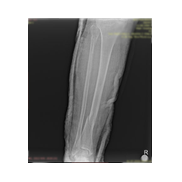

Görüntüleri büyütmek için resmin üstüne tıklayınız.